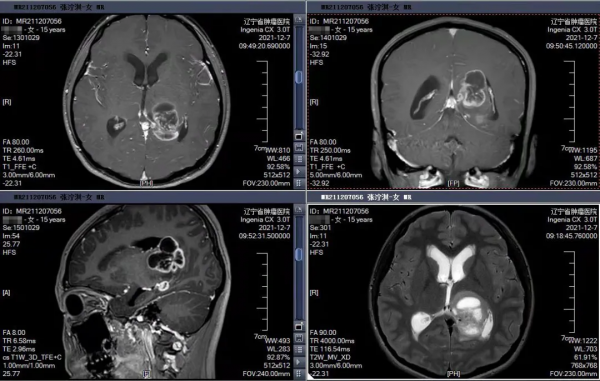

患者,女性,15歲,以“雙眼視物重影一週”為主訴入院,經診斷為丘腦後部腫瘤——能否在不損傷重要功能的情況下,徹底切除腫瘤成為手術成功的關鍵。術前,神經外科姚冰主任醫師治療組與醫學影像科通力合作,反覆研究最佳化磁共振掃描序列,嚴密設計了導航方案。手術過程中,樸浩哲教授在神經導航的引導下進行精準定位,同時應用熒光素鈉對腫瘤進行染色,確定腫瘤組織的邊界和範圍,輔助手術醫生最大程度、安全可靠地完成腫瘤的切除。對於術中因腦脊液流失而導致的漂移情況應用術中超聲手段進行了動態監測,消除影像導航因組織形變造成漂移的誤差,成功精準的切除了全部腫瘤。患者術後恢復佳,沒有遺留任何後遺症。

術前的增強核磁共振影象,可見丘腦後部腫瘤

術後24小時複查的增強核磁共振影象

可見丘腦後部腫瘤全部徹底切除